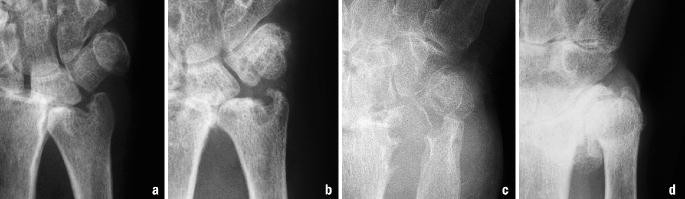

Abb 12a D Impressionsfraktur A B Frakturierte Processus Download Scientific Diagram

Figure 1 Een Man Met Niet Alleen Een Polsfractuur Springerlink